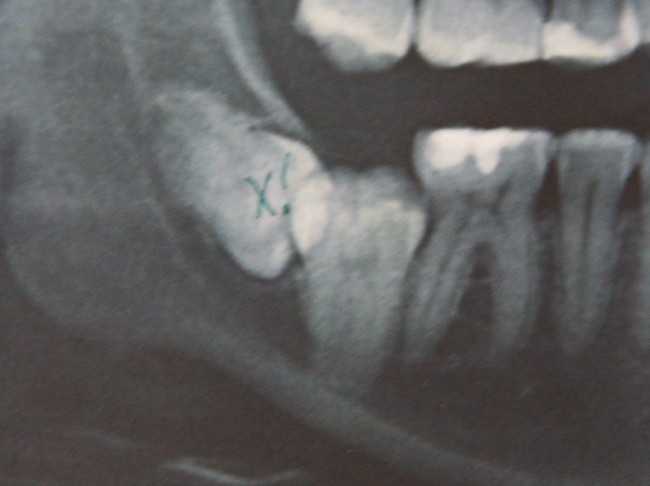

Однажды ко мне обратилась девочка по направлению от ортодонта. Принесла снимок:

Помимо аномального положения зуба мудрости есть еще одна проблема: восьмерка заблокировала седьмой зуб, в результате он не может прорезаться. В другой клинике ей предложили удалить два зуба, но она, по совету своего доктора, решила обратиться к нам в клинику.

Мы решили, что семерку можно вытянуть, если аккуратно удалить восьмерку.